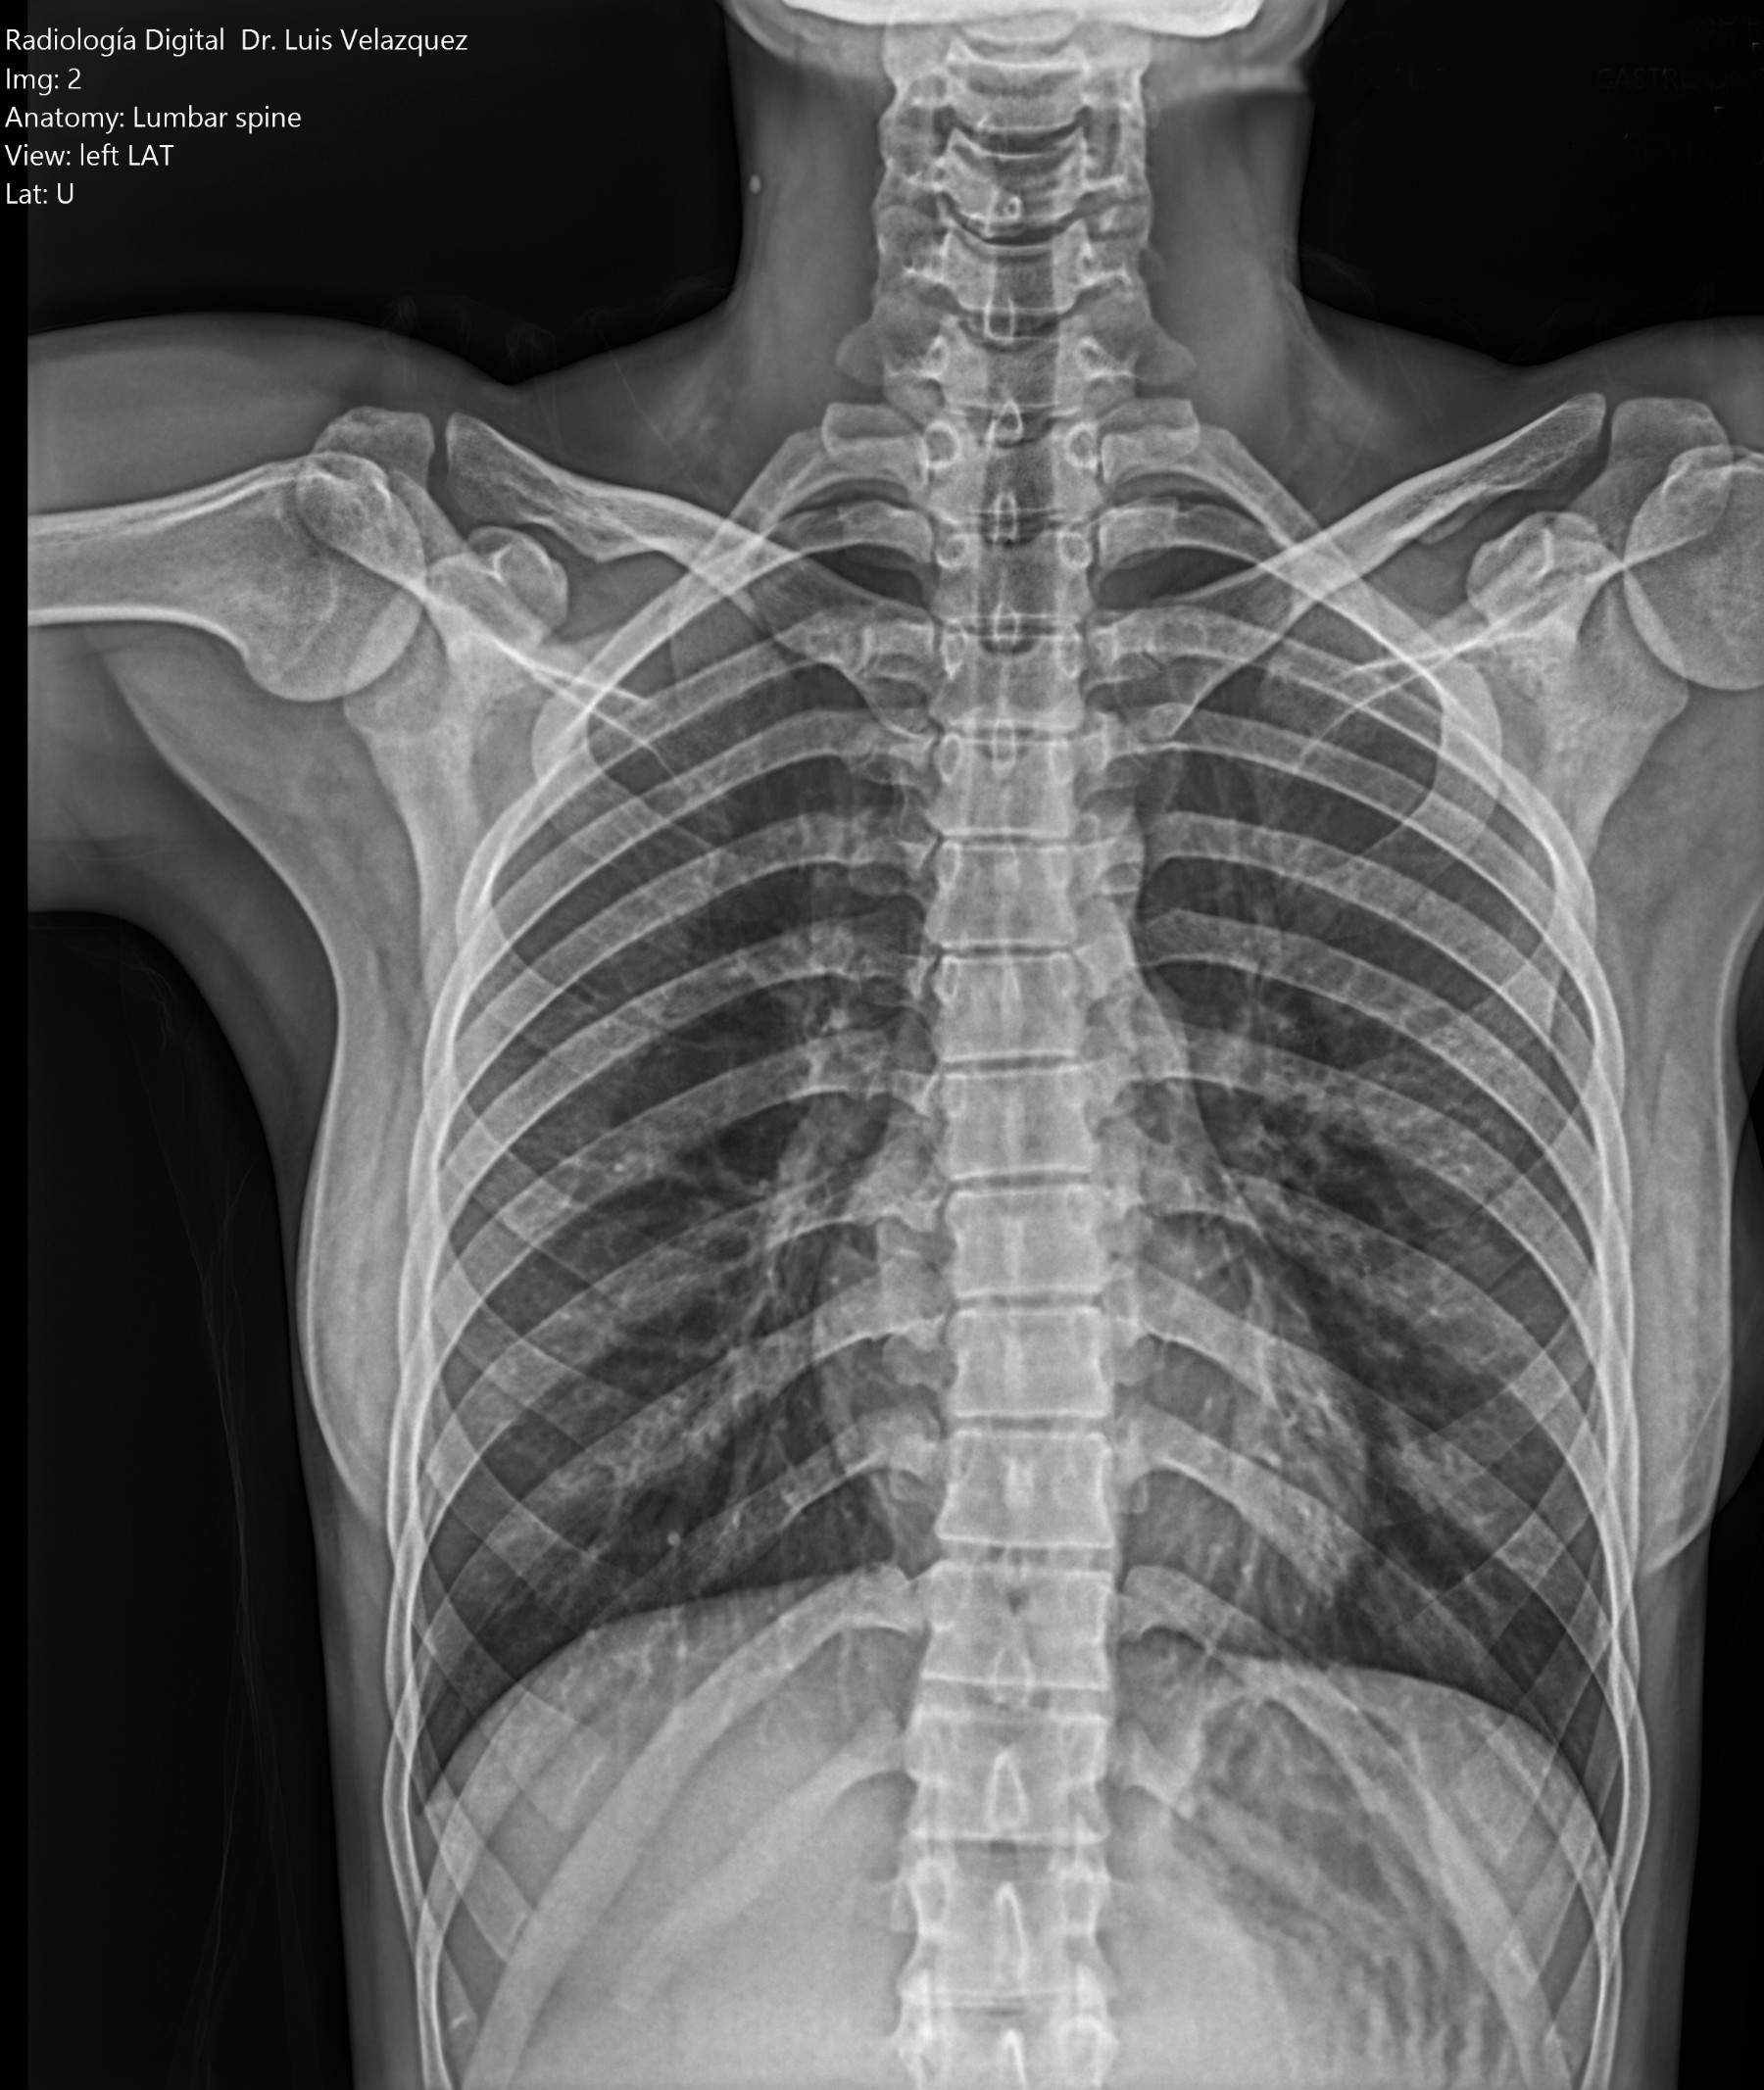

Radiología Digital como Herramienta Complementaria en el Dictamen de Bienes Muebles

Desde el descubrimiento de los rayos “X” y las placas radiográficas por Wilhelm Conrad Roentgen y su posterior difusión a través de la Asociación Físico médica de Wurzburg el 28 de diciembre de 1895, que fue la primera asociación que habló de los nuevos rayos que podían penetrar el cuerpo y fotografiar los huesos, ha habido muchos cambios tanto en la forma de obtener, procesar e incluso en la forma de visualizar, manejar y almacenar las placas radiográficas.